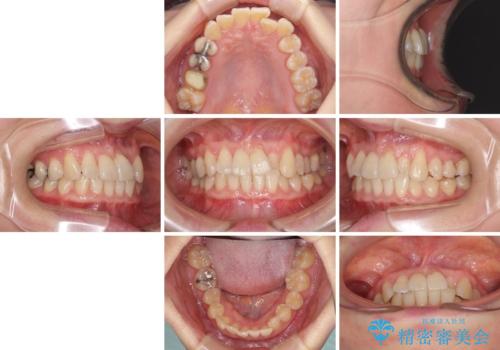

前歯のクロスバイト インビザライン矯正で改善

- むし歯治療を契機に、長年気にしていた前歯のクロスバイトの改善を希望された患者様です。

汚れが溜まりやすく、歯ぎしりがうまくできないため、インビザラインを用いて矯正治療を行うこととしました。

インビザラインによる前歯のクロスバイトの改善は、治療期間中に前歯でしか咬めない時期が続いたり、歯肉退縮や歯髄壊死のリスクが高まったりと、治療中にトラブルを抱えることがあります。

特に上顎側切歯(真ん中から2番目の歯)が舌側に引っ込んでいるケースは、インビザラインでは改善しきれないことがあると言われています。